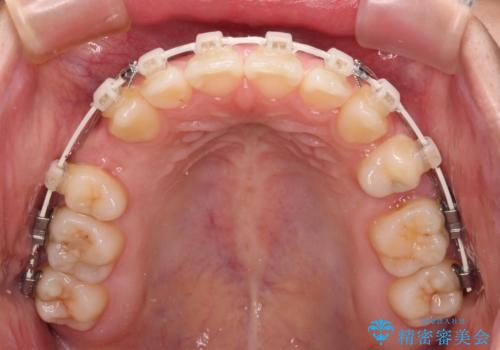

- 審美装置

- 2年6ヶ月

- 口元の突出感と上下前歯のズレを気にして来院された患者様です。

舌の突出癖により上下の前歯は非接触となっている状態でした。

舌のトレーニングを行わないと上下前歯の接触達成は困難であるため、トレーニングをしっかりと行っていただきながら、治療を進めて行くこととしました。

突出感改善のため、上下左右の第一小臼歯4本を抜歯し、ワイヤー装置にて矯正治療を行うこととしました。